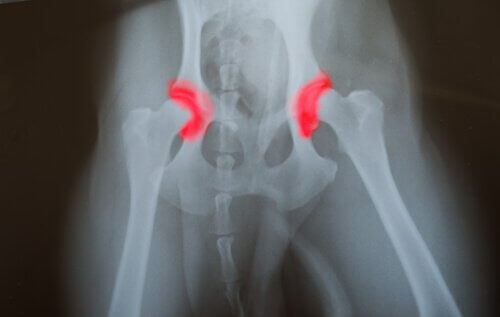

Dysplasi i hoften eller albuen er en arvelig sykdom. Dette er noe som blir overført fra generasjon til generasjon. Dysplasi er når to bein som sammen lager ett ledd, enten det er snakk om hofteledd eller albueledd, ikke befinner seg i en korrekt posisjon.

På grunn av dette vil beina gnis mot hverandre. Man vil ikke klare å bevege dette leddet på en normal måte. Dette vil føre til at disse beina slites ned fortere enn normalt. Ettersom at dette leddet ikke fungerer som normalt, vil dette føre med seg andre problemer. Problemet med denne sykdommen er at den ikke er så lett å oppdage før det allerede er for sent.